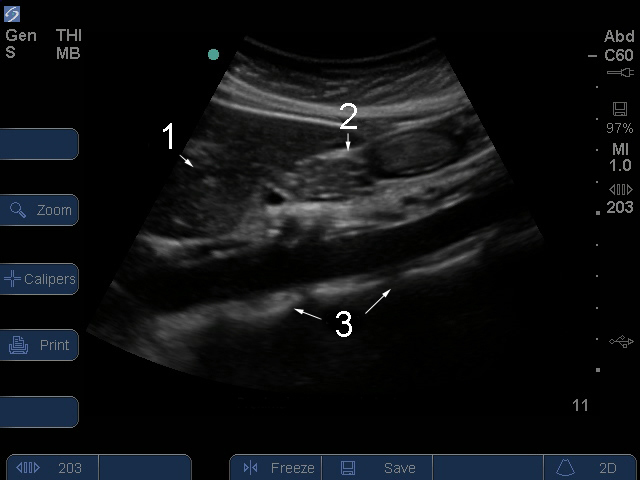

Proximale Aorta abdominalis

1. Leber

2. Bauchspeicheldrüse

3. Wirbelsäule